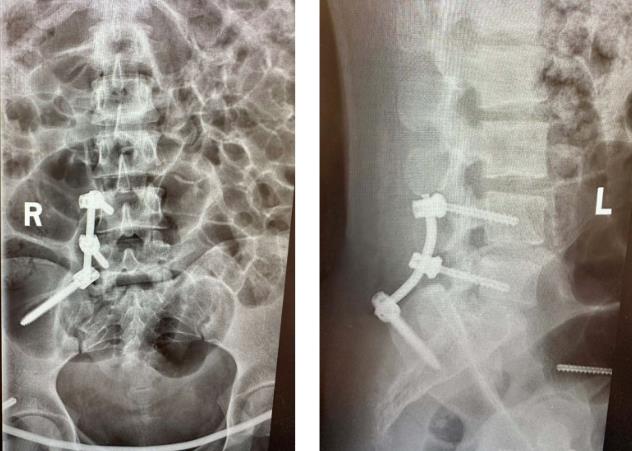

术中,医生采用前后联合入路共切开了3个微小切口,在C形臂X光机透视定位下复位、植入腰髂钉棒+前环钉棒系统,完成了对骨盆骨折的治疗,手术过程顺利。手术对患者的损伤小,组织剥离少,未伤到重要神经、血管,且出血少,术后患者双下肢活动良好,经过一系列的术后护理及康复锻炼,目前已康复出院。

▲术后复查X线